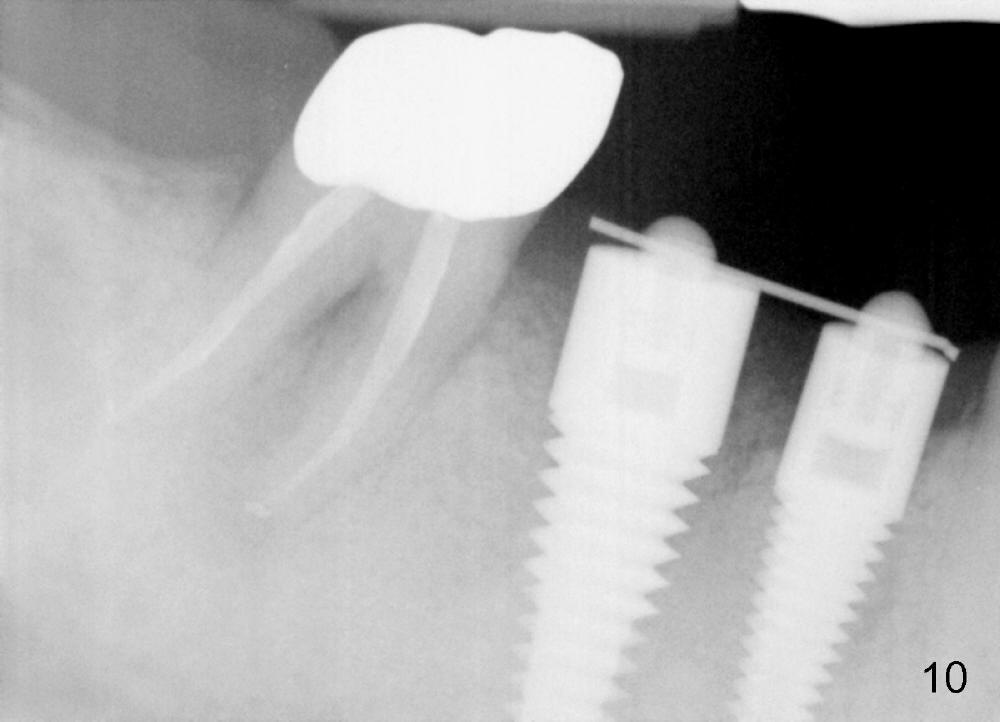

In 3 months, the gingiva appears to have grown up to cover more of the most coronal portion of the implants (Fig.9). Since the tooth #31 becomes symptomatic probably due to overloading (Fig.10), these 2 implants are prepared for restoration ahead of time.